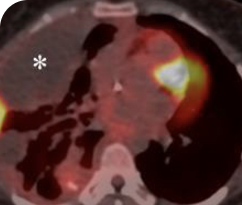

Clinical presentation1

- Initially diagnosed at age 27

- Bulky disease in neck and thoracic involvement; metastatic, RAI-refractory papillary thyroid cancer

Response to VITRAKVI1,2

- Confirmed partial response (92.6% reduction in target lesions)

- Treatment continued for 55 cycles

- VITRAKVI was well tolerated; patient did not have to discontinue due to AEa

- No treatment interruptions or dose reductions

Response in primary and metastatic lesions1

Images courtesy of Dr Steven Waguespack.